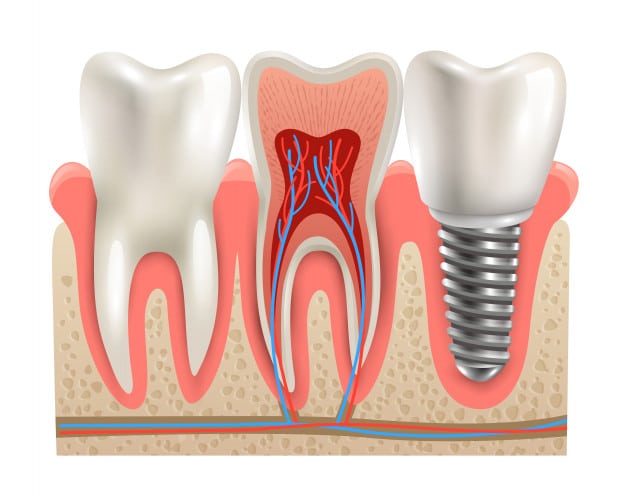

Tooth decay is a disease that results in the destruction of the enamel, the hard outer layer of the tooth. In order for cavities to develop there must be a host, a dietary substrate, and an aciduric bacteria.

Teeth are the host. Teeth are susceptible to decay as early as six months when the first tooth erupts in the month.

Proper care, treatment and restorations are necessary and critical to preventing the decay from becoming worse.